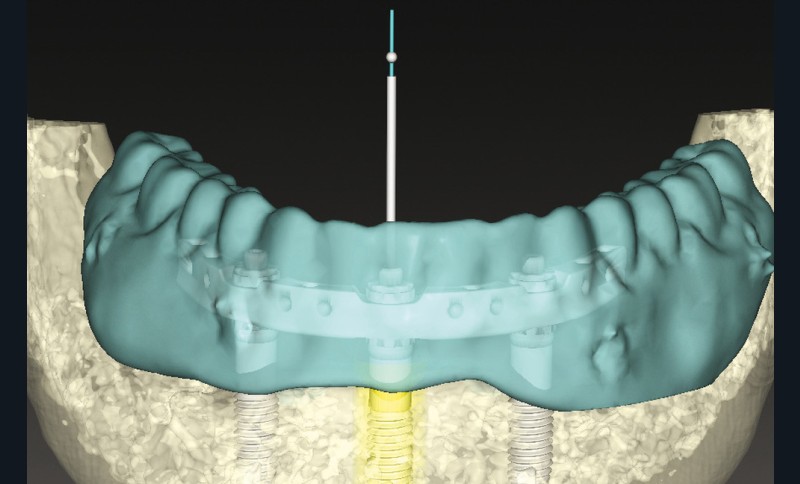

La planification virtuelle implantaire s’ensuit. Une fois encore, le numérique conforte ses atouts. Les matchings, sous réserve d’une parfaite correspondance, offrent une multitude d’informations optimisant la parfaite concordance entre anatomie osseuse, implants (3 CC RP 5×11,5mm), barre Trefoil et montage directeur (fig. 3). Cette somme d’informations permet alors de visualiser la barre Trefoil au travers du montage directeur.

La prothèse mandibulaire virtuelle recouvre parfaitement la barre digitale et les puits de vissage se trouvent en lingual des dents prothétiques. Cette prothèse pourra donc être conservée en tant que bridge d’usage, ce dernier étant dupliqué en guide radio-chirurgical implantaire de première intention. Turbine, contre-angle et cheville sont connectés en haut débit !